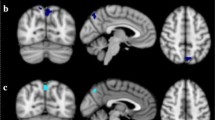

To assess how hypothalamic microstructural integrity is related to rs-FC of this brain region, three seed-based multiple linear regression functional connectivity analyses were performed. For each ICVF, OD, and ISOVF, we found a significant impact on hypothalamic functional connectivity to a cluster comprising the amygdala, hippocampus, and brainstem, as well as a cluster containing the nucleus accumbens and caudate (largest significant clusters for each contrast, pcluster < 0.001). Here, OD and ISOVF were negatively correlated with functional connectivity of the hypothalamus to the hippocampus-amygdala regions, and ICVF was positively correlated with hypothalamic connectivity to these regions. In contrast, functional connectivity to the nucleus accumbens was positively associated with OD and ISOVF, and negatively with ICVF (Fig. 3). Hence, hypothalamic microstructural integrity was associated with functional connectivity changes of the hypothalamus with limbic brain regions (see Online Resource Table 2 for a complete list of significantly associated brain regions in these contrasts).

Resting-state functional connectivity of the hypothalamus as a function of hypothalamic microstructure (intracellular volume fraction, orientation dispersion, isotropic volume fraction), as determined by seed-based multiple regression analyses. The overlap of the clusters with all three parameters is displayed in triplanar view (x = 8, y = 11, z = 10, n = 362)